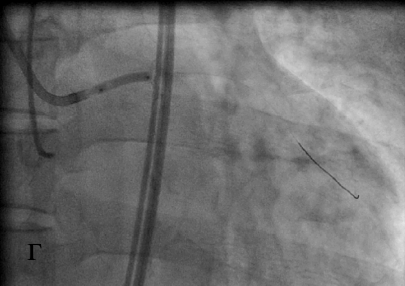

Коронарный проводник проведен за зону окклюзии, что подтверждено при выполнении коронарографии из ПКА (в), после чего выполнена баллонная ангиопластика окклюзированного ствола ЛКА (г). При контрольной коронарографии система ЛКА заполняется антеградно (д).